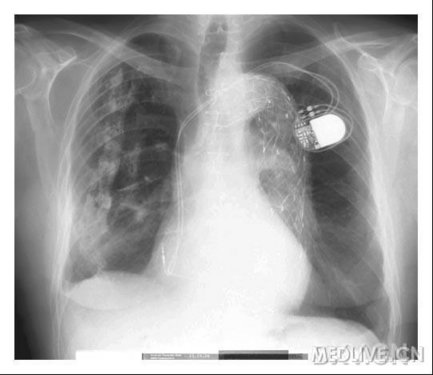

一张胸片上集中了近50年来医学的4项重大进展,您那你能指出来吗?

这是摘于以前一期的新英格兰杂志,您能指出该胸片集中了近50年来的哪4项重大进展呢?

杂志写道,这个问题共收到来自68个国家的729份回答,其中25%的答案完全正确,40%的答对其中的3个。

64%答对正中胸骨切开行冠状动脉搭桥,77%的答对 降主动脉支架植入,93%答对心脏起搏器植入。最后一个就只有39%的人答对最后一个····

64%答对正中胸骨切开行冠状动脉搭桥

77%的答对 降主动脉支架植入

93%答对心脏起搏器植入

只有39%的人答对肺叶萎陷疗法治疗结核